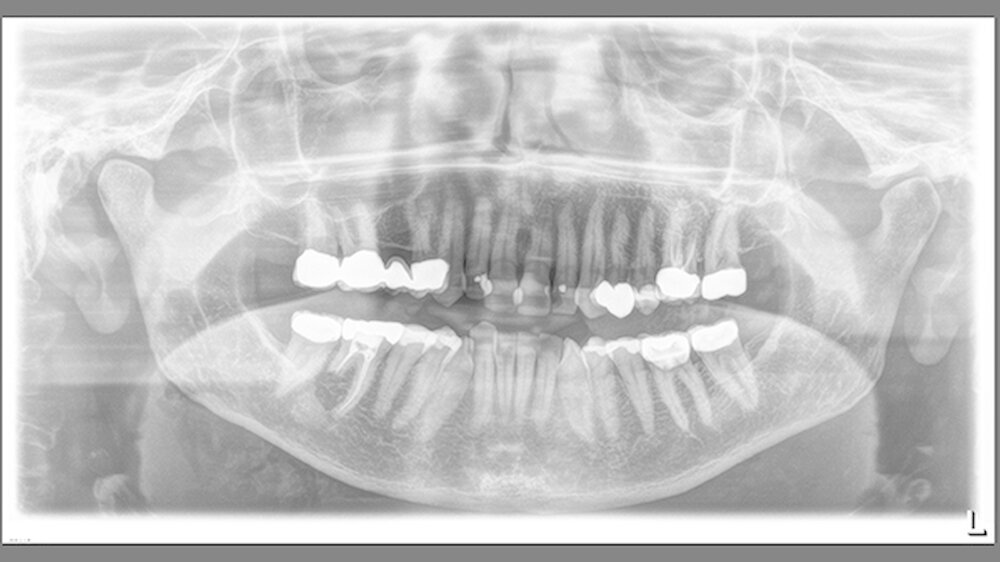

Aus der klinisch unauffälligen Spongiosa kam es intraoperativ zu einer sehr starken venösen Sickerblutung, die sich nach dreiminütiger Kompression spontan einstellte. Auf das Einbringen von Knochenwachs konnte somit verzichtet werden. Der cranial eröffnete Mandibularkanal wurde mit mehreren Lagen Kollagenvlies (Baxter) abgedeckt (im postoperativen OPT gut zu erkennen) und der Mucoperiostlappen konnte einschichtig speicheldicht vernäht werden.

Die postoperative Verlaufskontrolle war regelrecht, die Patientin beschwerdefrei, die Nahtentfernung erfolgte zehn Tage postoperativ ohne Probleme. Die histologische Beurteilung ergab ein „ungewöhnliches hochdifferenziertes komplexes Odontom".